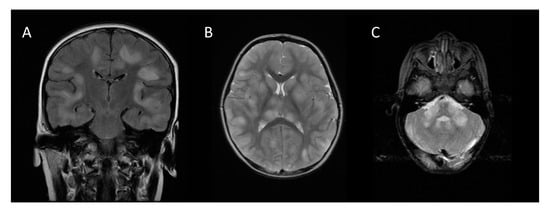

Brain MRI in the acute stage shows hyperintense abnormalities in T2-weighted and fluid-attenuated inversion recovery (FLAIR) images [4]. Lesions typically are bilateral, asymmetrical, large (>2 cm) and poorly demarcated. Both white and gray matter can be affected. Cortical as well as deep gray matter lesions have been described. Figure 2 shows some examples of typical ADEM MRI features. Gadolinium enhancement is not a typical feature of ADEM, reported in up to 30% of cases [14]. The frequency of spinal cord abnormalities is not well known, as spinal cord imaging is not routinely done in all ADEM cohort studies. If present, spinal cord abnormalities can be observed over more than two vertebral segments [14,35,38]. Complete resolution of MRI abnormalities has not been studied systematically, likely due to the need for sedation of young children for the procedure. This may be the reason for conflicting data on the resolution of MRI abnormalities [14,41,42].

Figure 2.

Typical magnetic resonance imaging features of ADEM: (A) coronal fluid-attenuated inversion recovery (FLAIR) image showing asymmetrical bilateral subcortical white matter abnormalities; (B) axial T2-weighted image depicting asymmetrical bilateral white and gray matter abnormalities; (C) axial T2-weighted image showing typical cerebellar peduncle lesions.

Notably, MRI may show no abnormalities in the first days [42]. Additionally, during clinical recovery, MRI imaging may still show worsening, indicating a lag between clinical symptoms and MRI abnormalities. As some patients with ADEM may have a multiphasic disease course and even develop MS, a reference scan timed around three months after ADEM onset is advised.